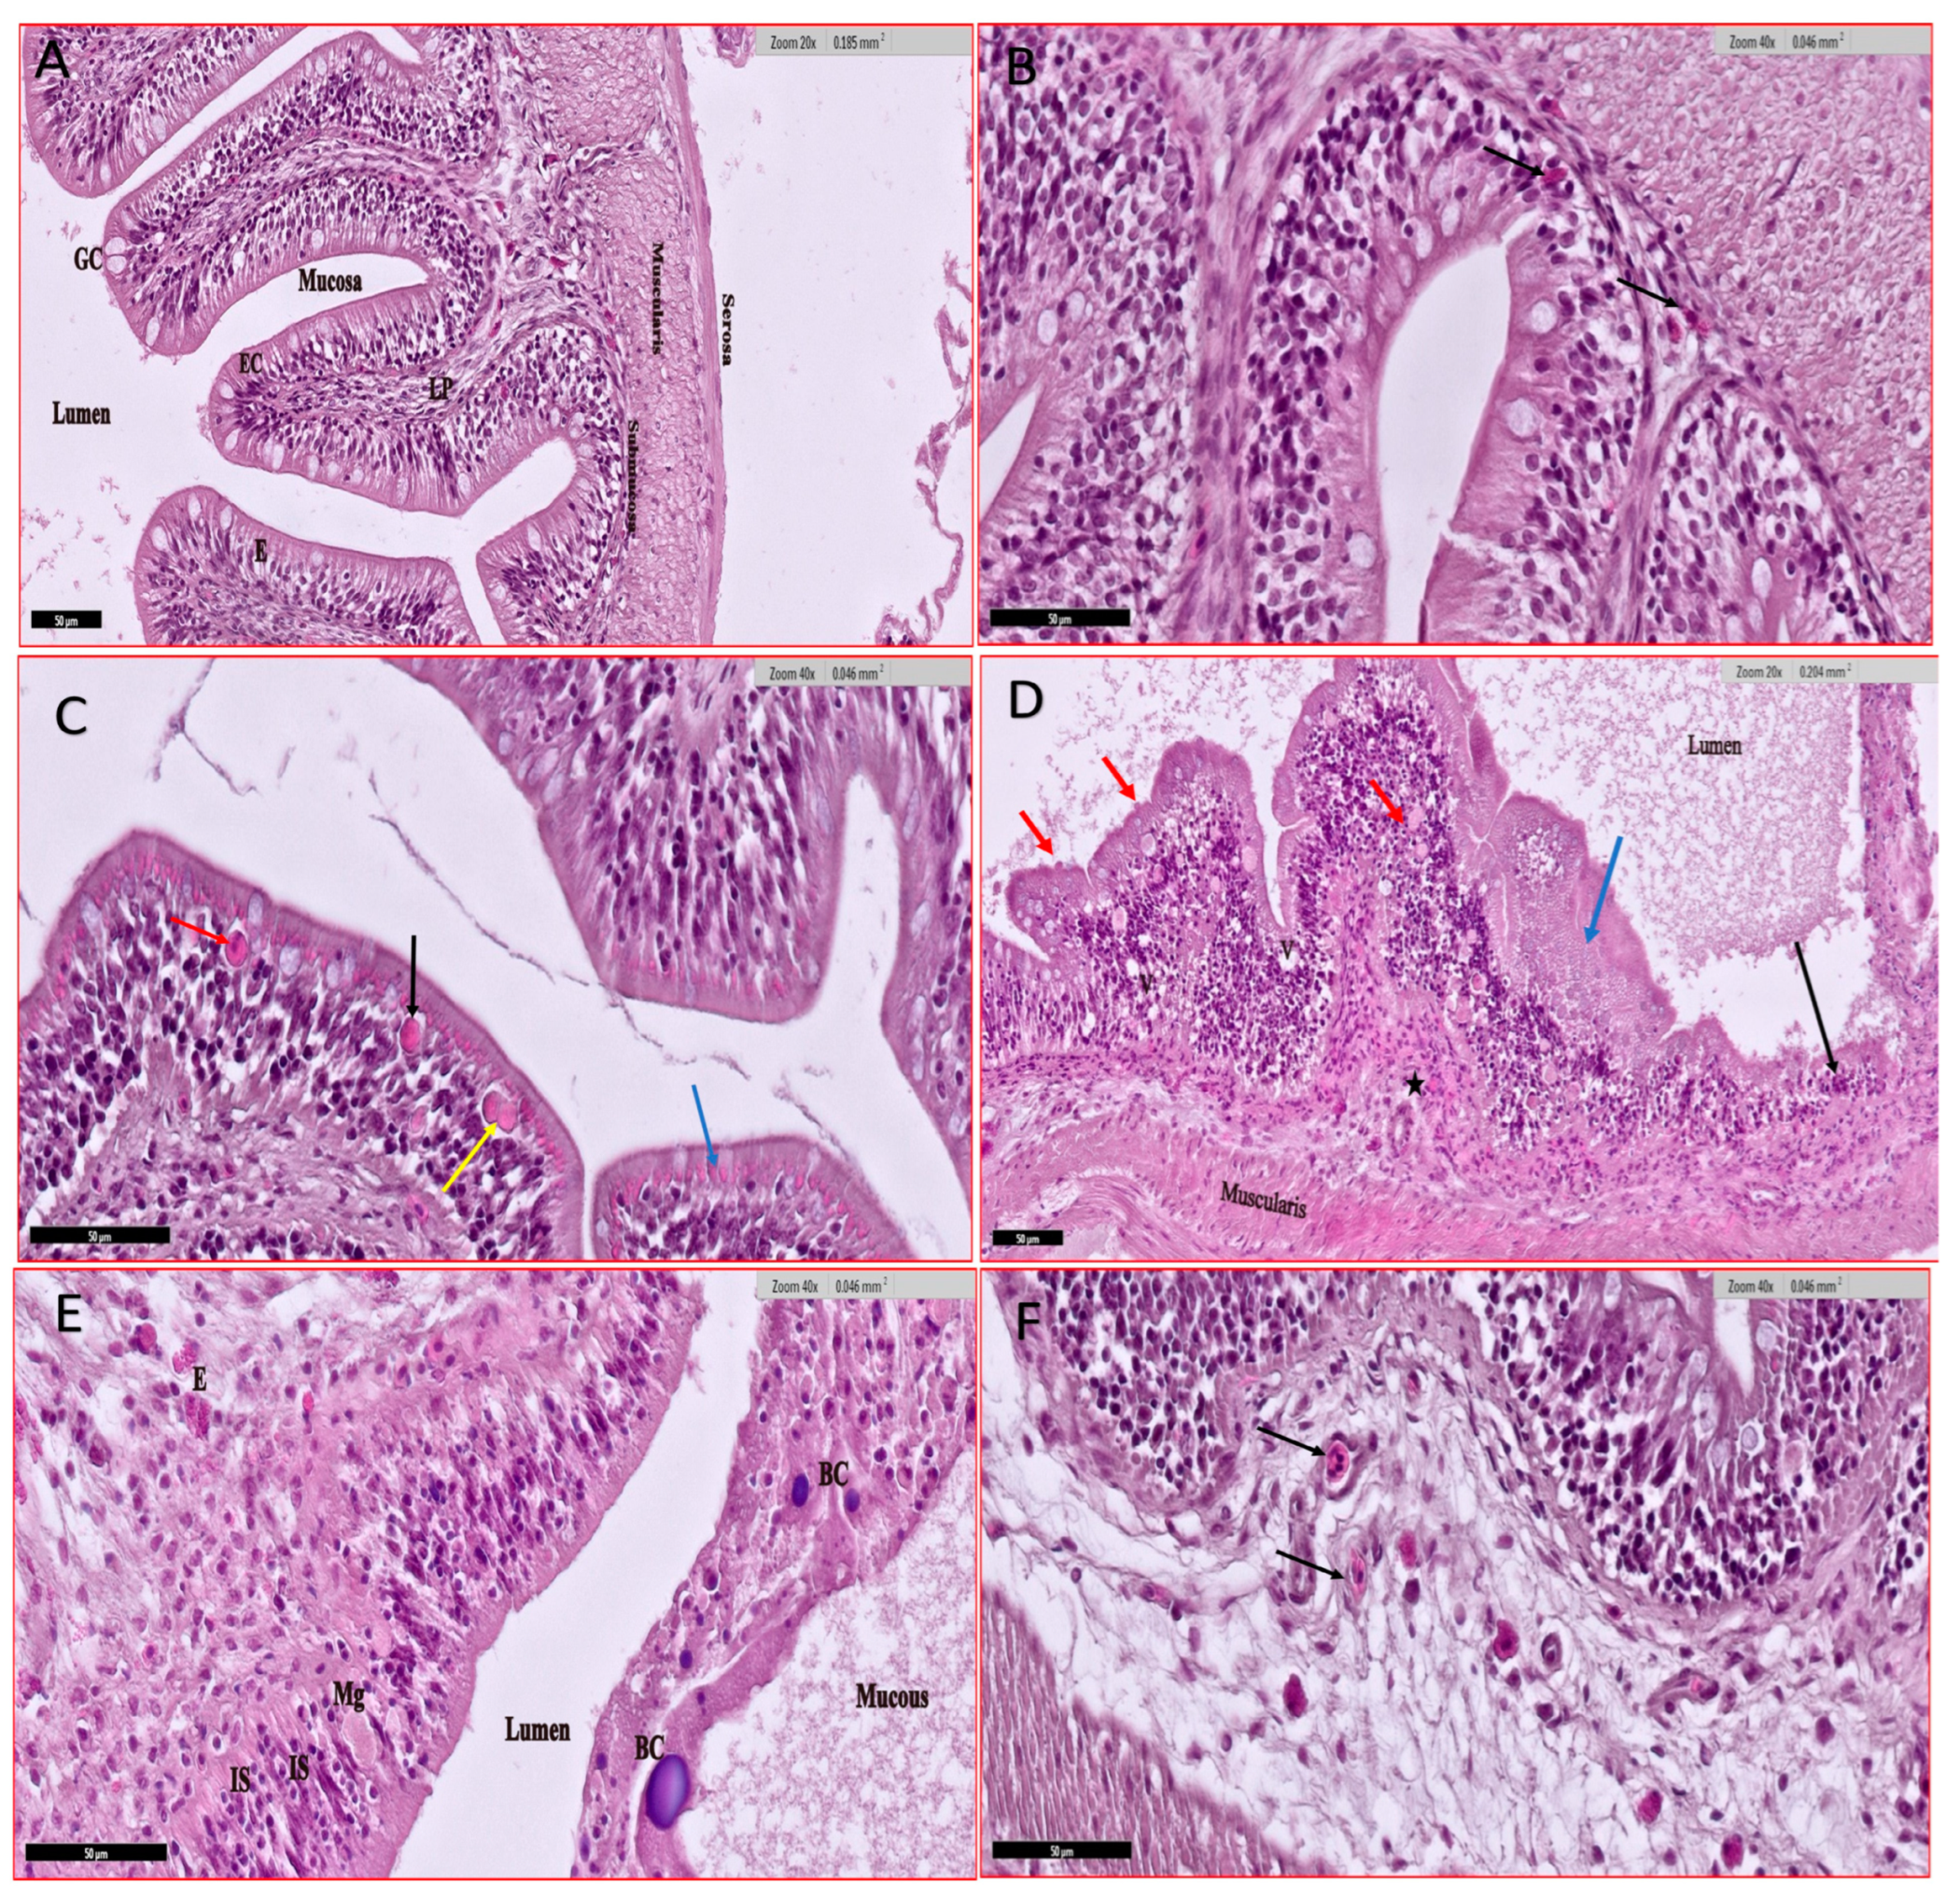

3.4.2. Gills

3.4.3. Intestine